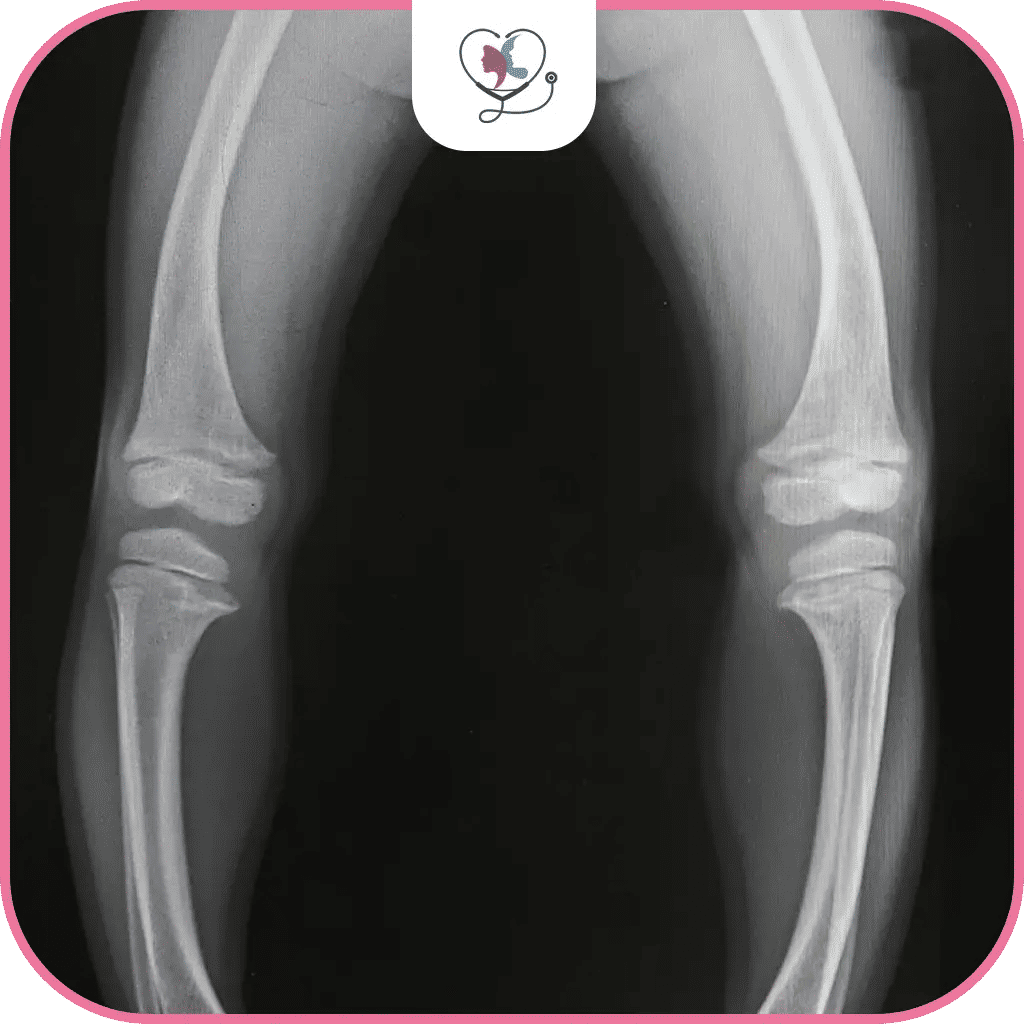

تقوس الساقين أو بالانجليزية Bow legged والمصطلح الطبي له Genu varum هو عبارة عن مشكلة طبية تكون فيها الأرجل مقوسة من ناحية الركبة، مما يبقي الركبتين متباعدتين عندما يكون الكاحلان ملتصقين ببعضهما، حيث إنّ الحالة الطبيعية هي أن يكون كلاً من الورك والركبة والكاحل على خط مستقيم وبنفس المستوى.

ولنوضّح الأمر أكثر؛ عندما ترسم خطاً مستقيماً من الورك إلى أسفل القدم، فإن هذا الخط يجب أن يمر بمنتصف الركبة، في حالة الإصابة بتقوس الساقين تكون الركبتان خارج هذا الخط المستقيم، أي أنهما لم يعودا على مستوى واحد مع الوركين والركبتين، فيكون شكلها كالقوس مسبباً إحراجاً في بعض الأحيان خصوصاً في فئة المراهقين والشباب.

تختلف درجة تقوس الساقين عند الكبار بشكل كبير، وتتراوح من تقوس بسيط إلى شديد. يتم تحديد درجة التقوس بناءً على المسافة بين الركبتين عند الوقوف مع ملامسة الكاحلين.

تصنيف درجات تقوس الساقين عند الكبار:

- الدرجة الخفيفة: المسافة بين الركبتين أقل من 7.6 سم.

- الدرجة المتوسطة: المسافة بين الركبتين تتراوح بين 7.6 - 15.2 سم.

- الدرجة الشديدة: المسافة بين الركبتين تتجاوز 15.2 سم.